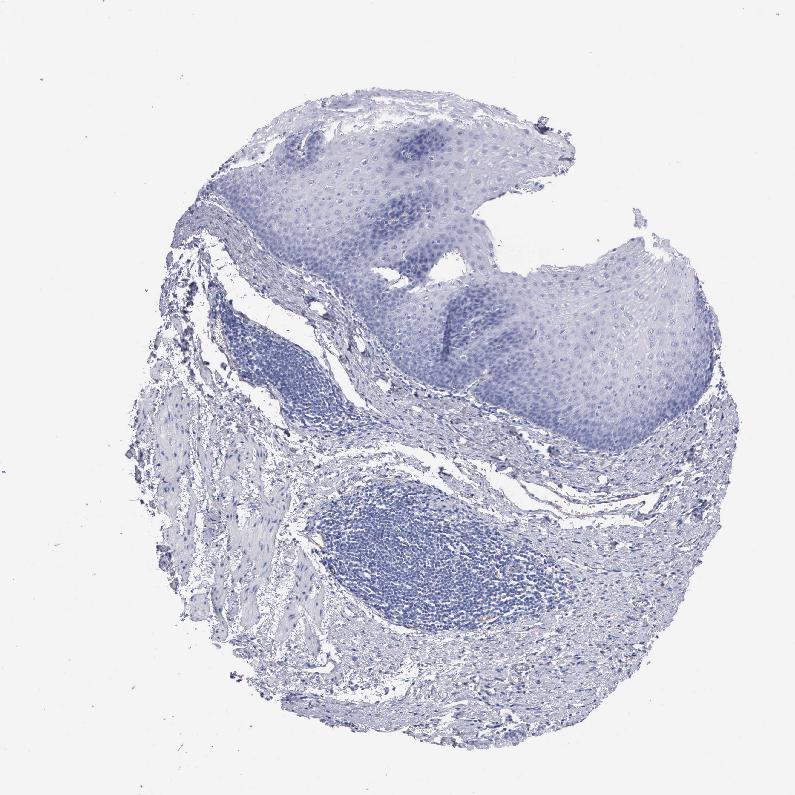

ESOPHAGUS - Antibody stainingi

Antibody staining in the annotated cell types in the current human tissue is reported as not detected, low, medium, or high, based on conventional immunohistochemistry profiling in selected tissues. This score is based on the combination of the staining intensity and fraction of stained cells.

Each image is clickable and will lead to virtual microscopy that enables deeper exploration of all samples and also displays staining intensity scores, fraction scores and subcellular localization as well as patient and tissue information for each sample.

Antibody HPA070413Antibody CAB000459

Squamous epithelial cells Not detectedNot detected